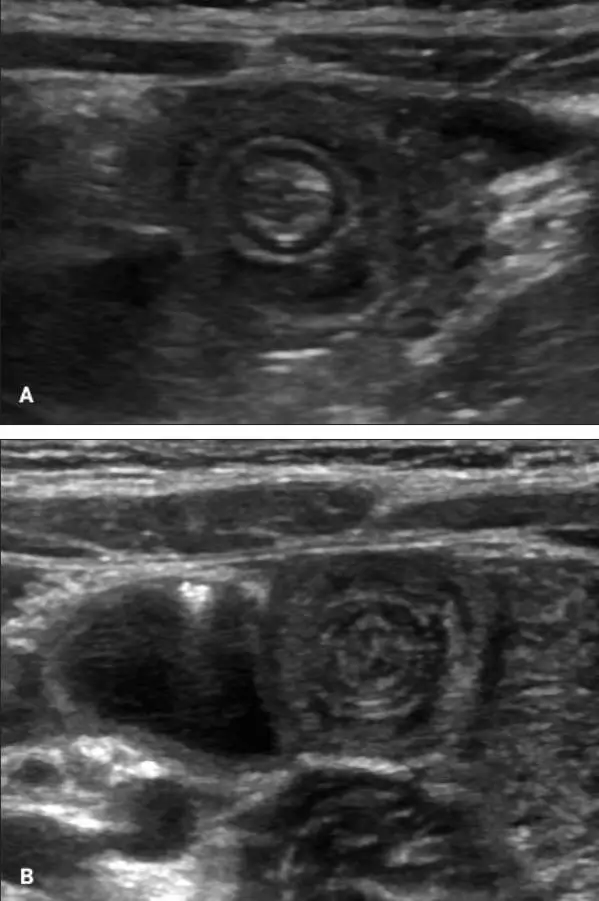

哎呀,说到这个肠套叠CT图,真是让人心惊胆战的!你知道吗,那种图一出来,医生们一个个都皱起了眉头,像是看到了什么不得了的大问题。我记得有一次,一个小朋友的家长拿着那张CT图来找我,脸上的表情比哭还难看。他们说,孩子肚子疼得厉害,做出来的CT图上,肠子就像是一条扭成了麻花的小蛇,真是让人看了心疼。

那图上的肠子,一层套一层,就像是玩偶里的小人儿,一个套一个,看得人眼花缭乱。医生说,这种情况要是不及时处理,孩子可是会有生命危险的。听到这话,家长的腿都软了,眼泪止不住地往下掉。我看着他们,心里也是五味杂陈,只能安慰说,医生们会尽全力救治的。